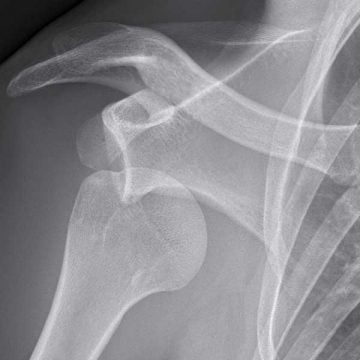

Radiologiska utredningar

Röntgenundersökning: Den vanligaste undersökningen efter att axeln gått ur led är en vanlig slätröntgen. Om axeln legat ur led i flera timmar kan det vara bra att komplettera med en datortomografiundersökning.